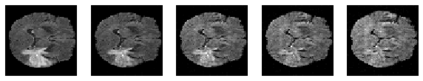

Disentangled representations can be useful in many downstream tasks, help to make deep learning models more interpretable, and allow for control over features of synthetically generated images that can be useful in training other models that require a large number of labelled or unlabelled data. Recently, flow-based generative models have been proposed to generate realistic images by directly modeling the data distribution with invertible functions. In this work, we propose a new flow-based generative model framework, named GLOWin, that is end-to-end invertible and able to learn disentangled representations. Feature disentanglement is achieved by factorizing the latent space into components such that each component learns the representation for one generative factor. Comprehensive experiments have been conducted to evaluate the proposed method on a public brain tumor MR dataset. Quantitative and qualitative results suggest that the proposed method is effective in disentangling the features from complex medical images.